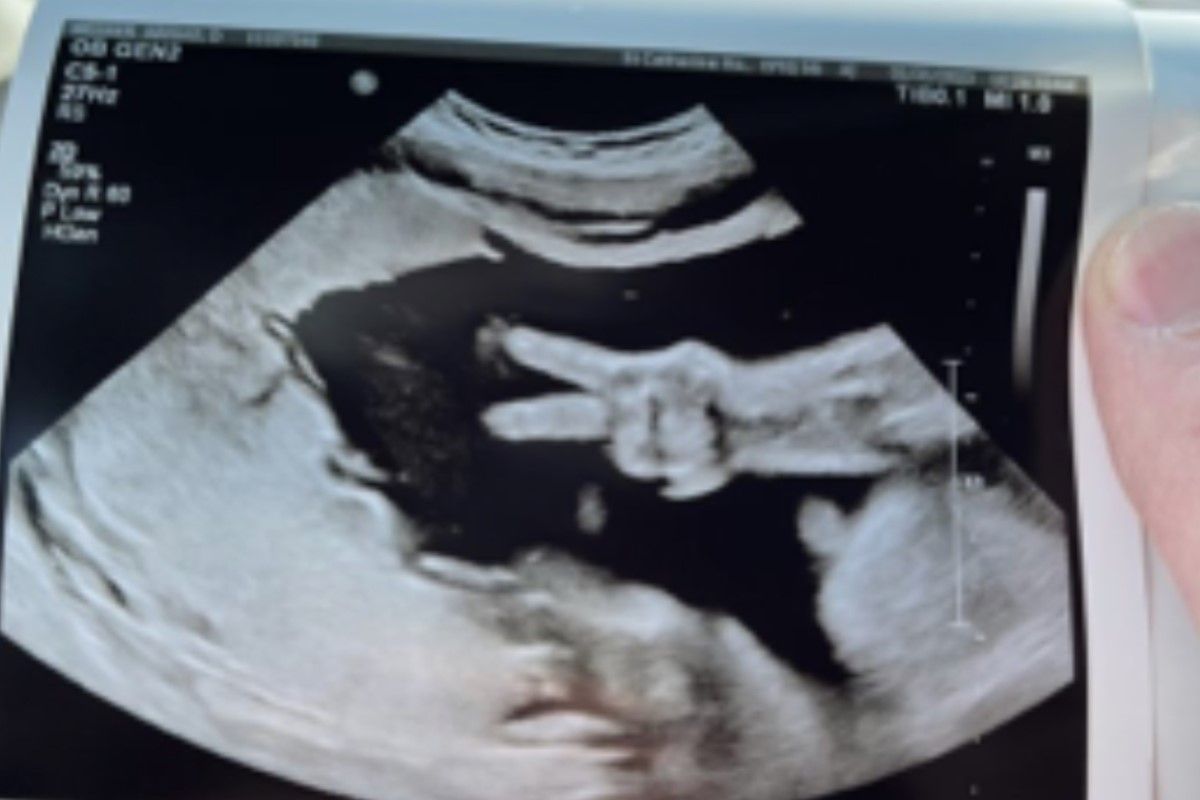

真是個快樂寶寶!美國印第安納州的一名孕婦日前進行例行產檢,正與醫師一同透過超音波觀察胎兒狀況,沒想到肚中小朋友竟突然比出「YA手勢」,讓媽媽和醫生都直呼神奇。

據外媒報導,媽媽艾比蓋維娜(Abigail Weener)目前已懷胎31週,距多數產婦的預產期只相差9週,她上個禮拜前往聖凱瑟琳醫院(St. Catherine Hospital)做例行產檢,在進行超音波檢查時,肚中胎兒突然豎起食指和中指,看起來就像在與爸爸媽媽比YA。

▲美國孕婦做產檢,發現肚中胎兒竟透過超音波向外面的爸爸、媽媽比YA打招呼。(示意圖/unsplash) 寶寶神奇的行為令現場所有人都又驚又喜,除了這對夫婦感到開心外,一旁的醫師也嘖嘖稱奇,表示行醫多年從未看過有寶寶比出YA手勢,是件獨一無二的幸事。

丈夫凱爾(Kyle Weener)說明夫妻二人為虔誠的基督教徒,對於女兒的舉動,他認為這是在向爸爸媽媽打招呼「我過得非常好,正在媽媽肚子裡健康成長」,他也感性表示,女兒是上帝送給他們最棒的禮物之一。(編輯:李惠婷)